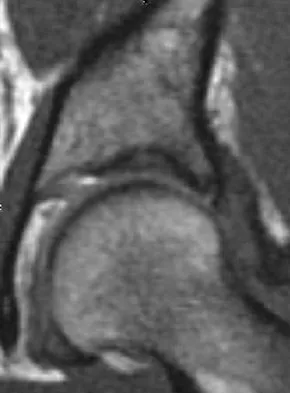

A 28-year-old woman who is an avid runner reports pain about the left hip with activities. Nonsurgical management has failed to provide relief. An MRI arthrogram is shown in Figure 47. What is the most likely diagnosis?

Explanation

The MRI arthrogram reveals dye extravasation into the labrum, consistent with a labral tear. The MRI findings are not typical of osteonecrosis, stress fracture, or transient osteoporosis. There is no increase in bone marrow edema in the neck or femoral head. Guanche CA, Sikka RS: Acetabular labral tears with underlying chondralmalacia: A possible association with high-level running. Arthroscopy 2005;21:580-585.

References:

- McCarthy JC: The diagnosis and treatment of labral and chondral injuries. Instr Course Lect 2004;53:573-577.